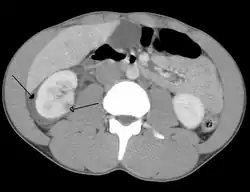

Abdominal trauma resulting in a right kidney contusion (open arrow) and blood surrounding the kidney (closed arrow) as seen on CT

Kidneys

A large hematoma (closed arrow) of the left kidney (open arrow)

The kidneys may also be injured; they are somewhat but not completely protected by the ribs.[6] Kidney lacerations and contusions may also occur.[13] Kidney injury, a common finding in children with blunt abdominal trauma, may be associated with bloody urine.[13] Kidney lacerations may be associated with urinoma or leakage of urine into the abdomen.[4] A shattered kidney is one with multiple lacerations and an associated fragmentation of the kidney tissue.[4]